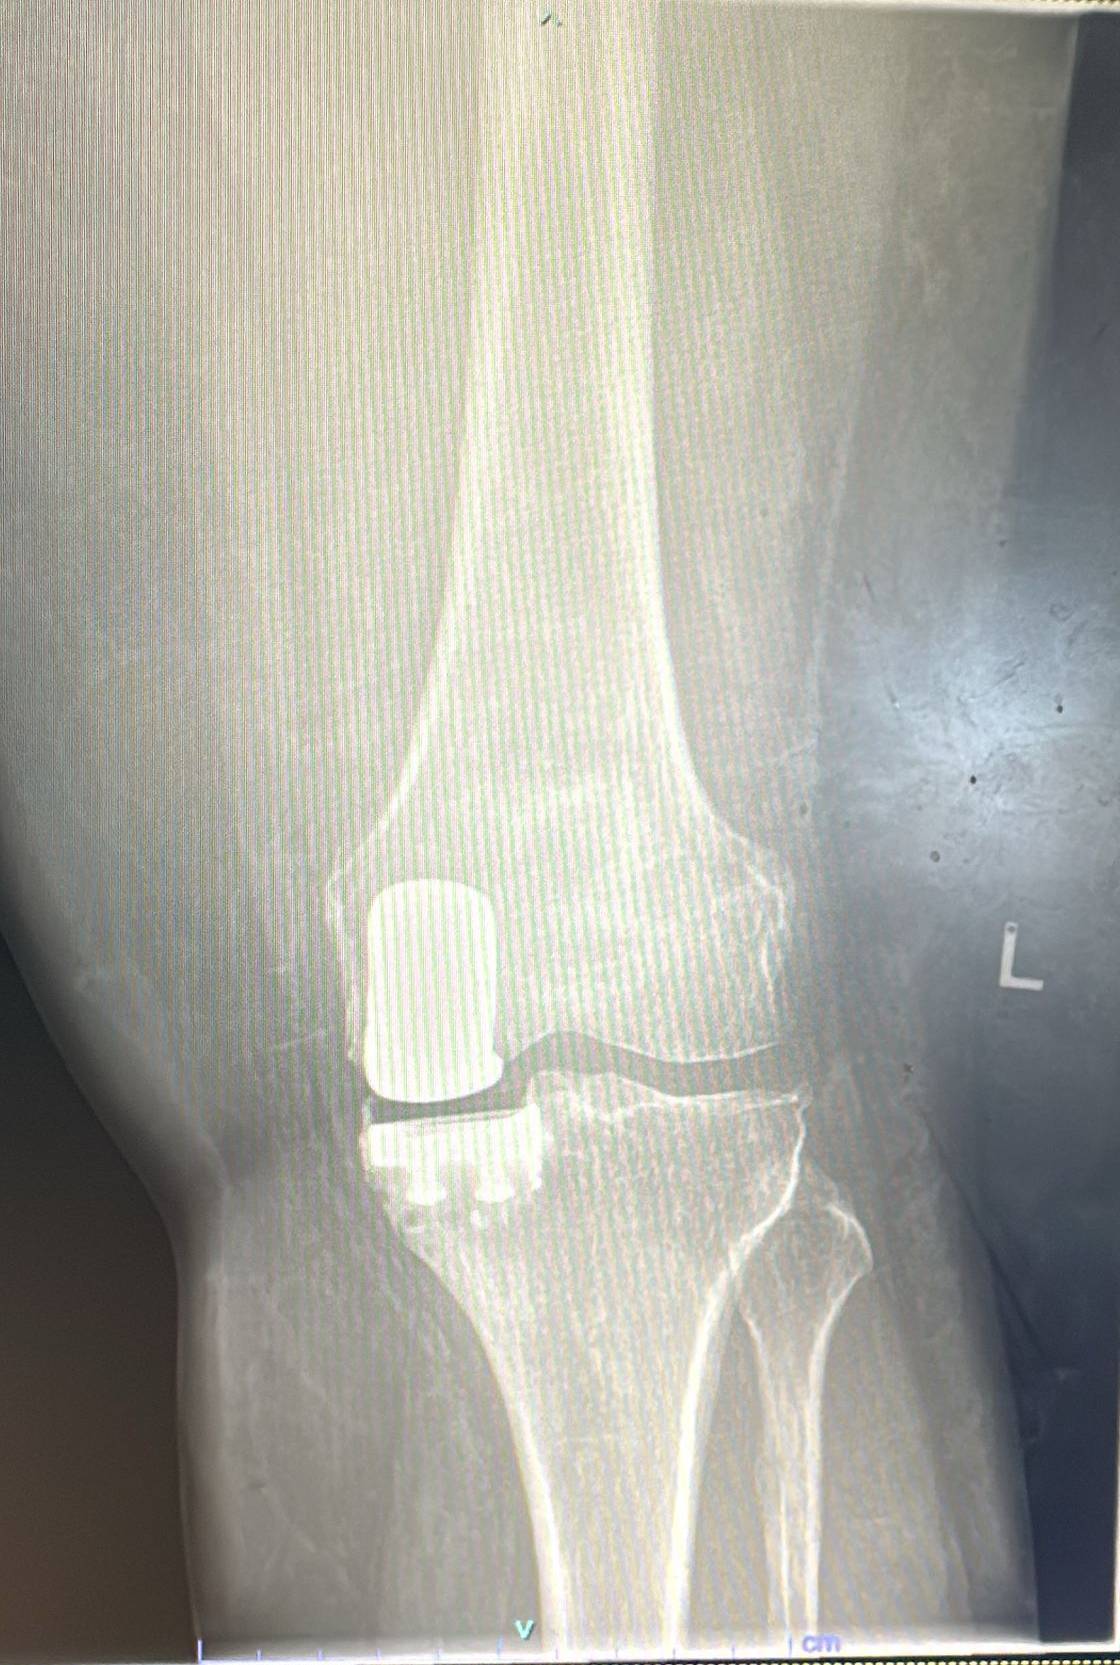

Zimmer Persona: Advanced Partial Knee Replacement

The Zimmer Persona platform delivers bone-preserving, ligament-sparing solutions for patients with isolated knee compartment arthritis. Enjoy faster recovery and superior outcomes.

Zimmer Persona is an advanced partial knee replacement system designed for patients with arthritis limited to one compartment of the knee. It preserves healthy bone and natural ligaments while providing excellent pain relief and functional outcomes.

- ✓Zimmer Persona implant insertion and alignment